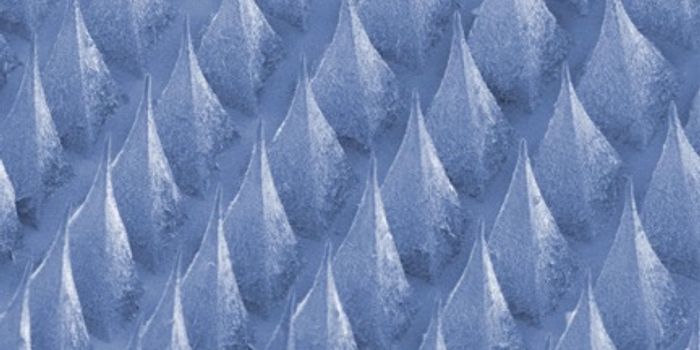

OCT 13, 2017Clinical & Molecular DXDespite frequent cleaning and sterilization, hospitals are notorious hotspots for germs and pathogens. And it’s no ...

OCT 29, 2016Clinical & Molecular DXDespite frequent cleaning and sterilization, hospitals are notorious hotspots for germs and pathogens. And it’s no ...